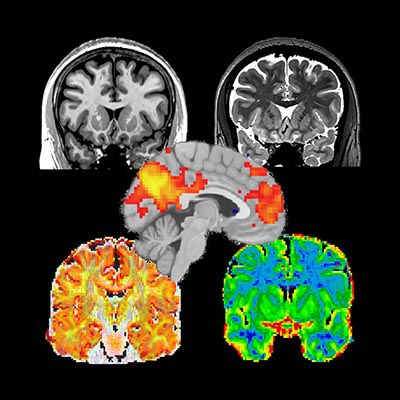

Acquisition Protocols

Recent advances in MRI scanner design provide for new sophisticated scan protocols for high resolution multi-modal data. Here we provide a protocol developed for a Brain Canada project acquiring MRI data on the MNI’s new Siemens Prisma 3T from individuals with interesting genetic alterations.